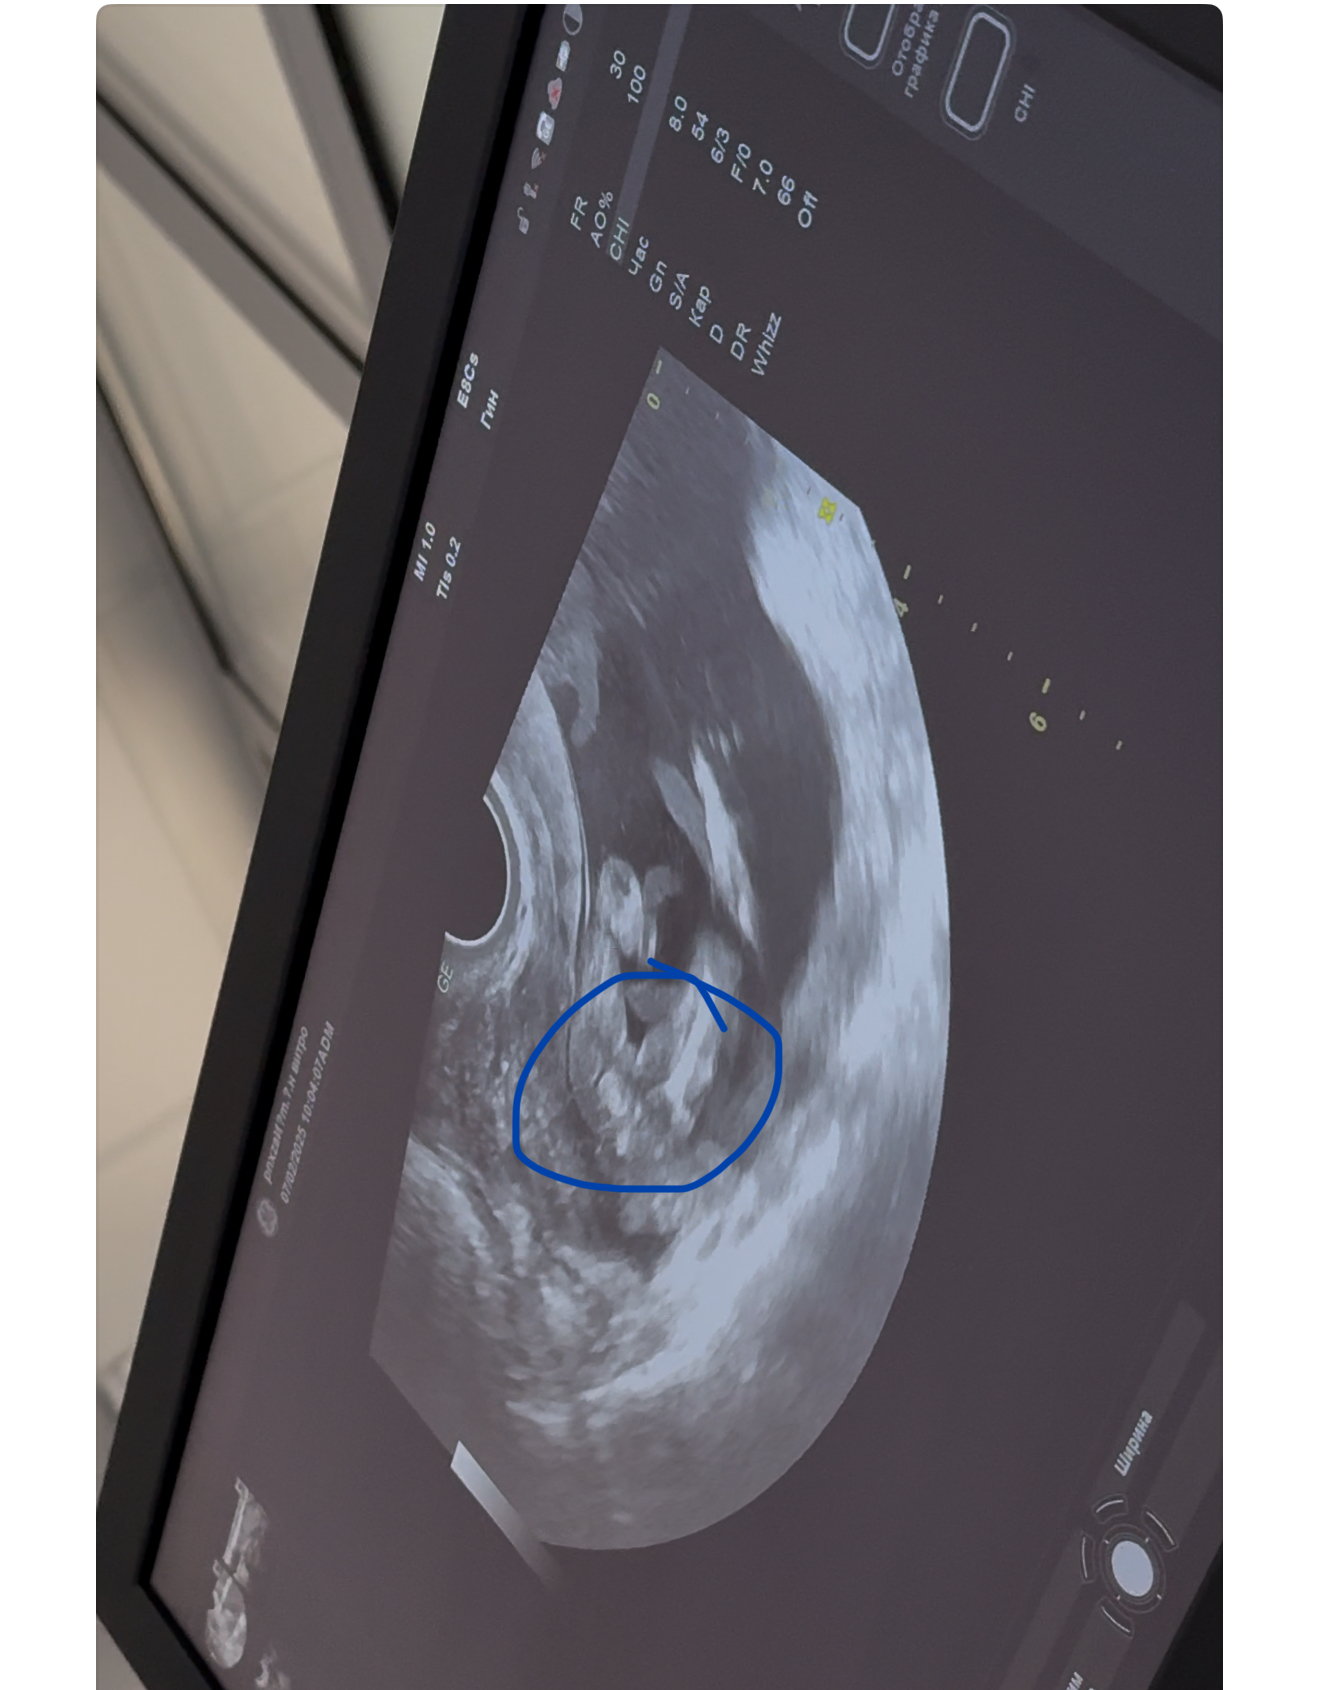

Кто в теме, подскажите пжста, веду беременность платно, на первом скрининге за пол я не спрашивала, так как понимала что срок маленький совсем. На 11 неделе делали. Далее перед отпуском решила сходить сделать узи платно, подсмотреть так сказать за малышом)) Было 14 - почти 15 недель. Я шла просто подсмотреть! А узист закончив первые важные замеры, спросила а не говорили ли мне уже пол? Я ответила что нет, маленький ведь срок. На что она мне сказала ну тут уже все очень даже видно, мальчик у вас будет! Заявила на все 100% и все оставшееся время пока мы там все рассматривали , ручки ножки, она раз 10 сказала что пистолетик видно 😂 Прям уверила . Но мне, честно, тоже показалось сразу это самое, как только началось узи. Фото приложу. И вот вернулась я с отпуск, думаю схожу еще раз , а то второй скрининг только 12 марта. И что вы думаете? В этот раз она молчала на счет пистолетика про который твердила в первый раз 🙈🫠 17 недель и 3 дня по последний мес 🩸 и по малышу написала 16 недель 9 дней. Как в аптеке 😅 Сказала что-то сегодня не видно ничего. Короче малость я расстроилась конечно.. когда тебя так сильно уверяли, а сегодня вот такое) Еще и фотку распечатала пистолетика, сказала мужу показать) эхх Все фото это 14-15 недель